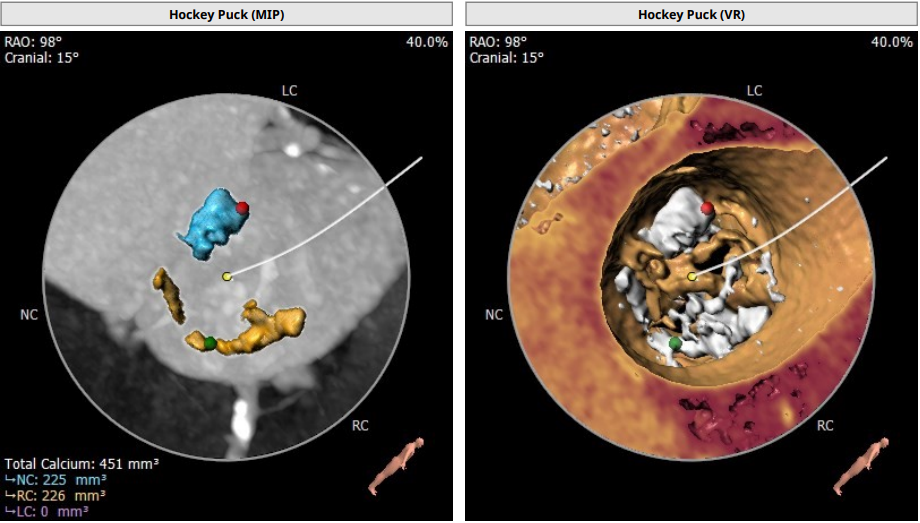

瓣环平均直径:18.5 mm,左室流出道平均直径:18.6 mm

主动脉根部:TYPE0型二叶瓣,瓣叶增厚,中度钙化,钙化主要集中在瓣叶上,瓣环及流出道可见钙化延伸,右冠高度约12.3mm,左冠高度约 13.1mm,法式窦结构较小,STJ高度约19.5mm,直径约29.7mm,升主动脉可见增宽,最宽处约43.5mm,心脏角度呈横位,约 76°,建议备Snare,心肌肥厚,左室较小(自杀左心室),存在循环奔溃风险,建议术前及术中注意补液,工作体位:CRA:29°。不建议预扩,标准位释放。入路:主动脉弓部走行迂曲,角度约83°,无名动脉、左颈动脉、左锁骨下动脉起源自主动脉弓部,未见发育变异,降主动脉走形较平直, 管腔未见狭窄,双侧股动脉走形较平直,管腔未见狭窄,左侧股动脉分叉在股骨头下缘处,右侧股动脉分叉在股骨头下1/3处。